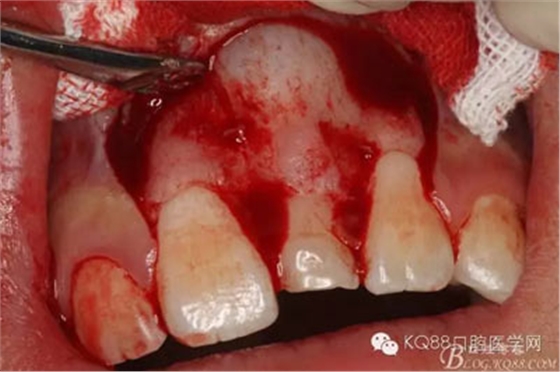

圖9.超聲骨刀去除隆起的骨壁

圖10.形成梯形骨縫